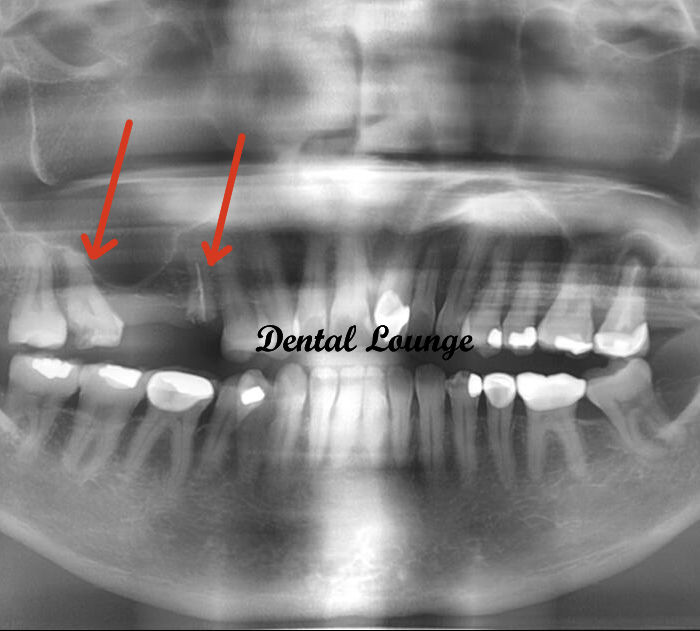

How do you know if I have retained roots?

X-rays or 3D imaging reveal fragments that may not be visible or causing symptoms yet.

Retained root surgery removes tooth root fragments that remain in the jawbone after tooth extraction or breakage. These fragments can cause pain, infection, or interfere with healing and future dental work. Our minimally invasive techniques ensure complete removal and proper healing.

Retained root removal is a routine surgical procedure used to extract fragments of tooth roots left behind after a fracture or incomplete extraction. The process begins with diagnostic imaging to locate the root and assess its depth. Under local anaesthesia, your dentist will access the area, remove any bone if necessary, and extract the root using precise instruments. The site is then cleaned, sutured, and allowed to heal. This straightforward treatment helps prevent infection, restores oral health, and prepares the area for future procedures such as dental implants. With modern techniques, most patients find the experience comfortable and recovery uncomplicated.